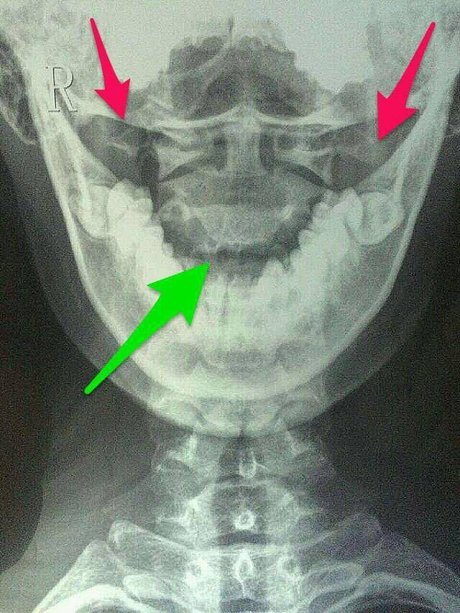

寰枢关节脱位的影像学诊断

寰枢关节半脱位x片

寰枢关节脱位图片

寰枢关节张口位